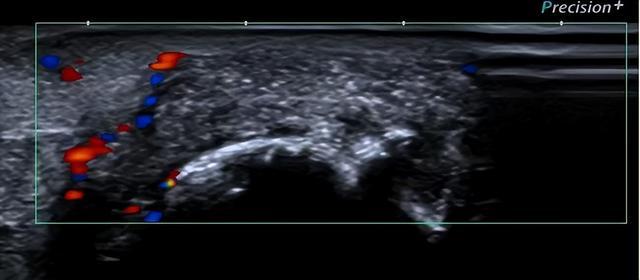

病例3 痛风石形成

▲软组织内可见高、低混杂回声、密度不均的团块影,CDFI:其周边可见点条状血流信号